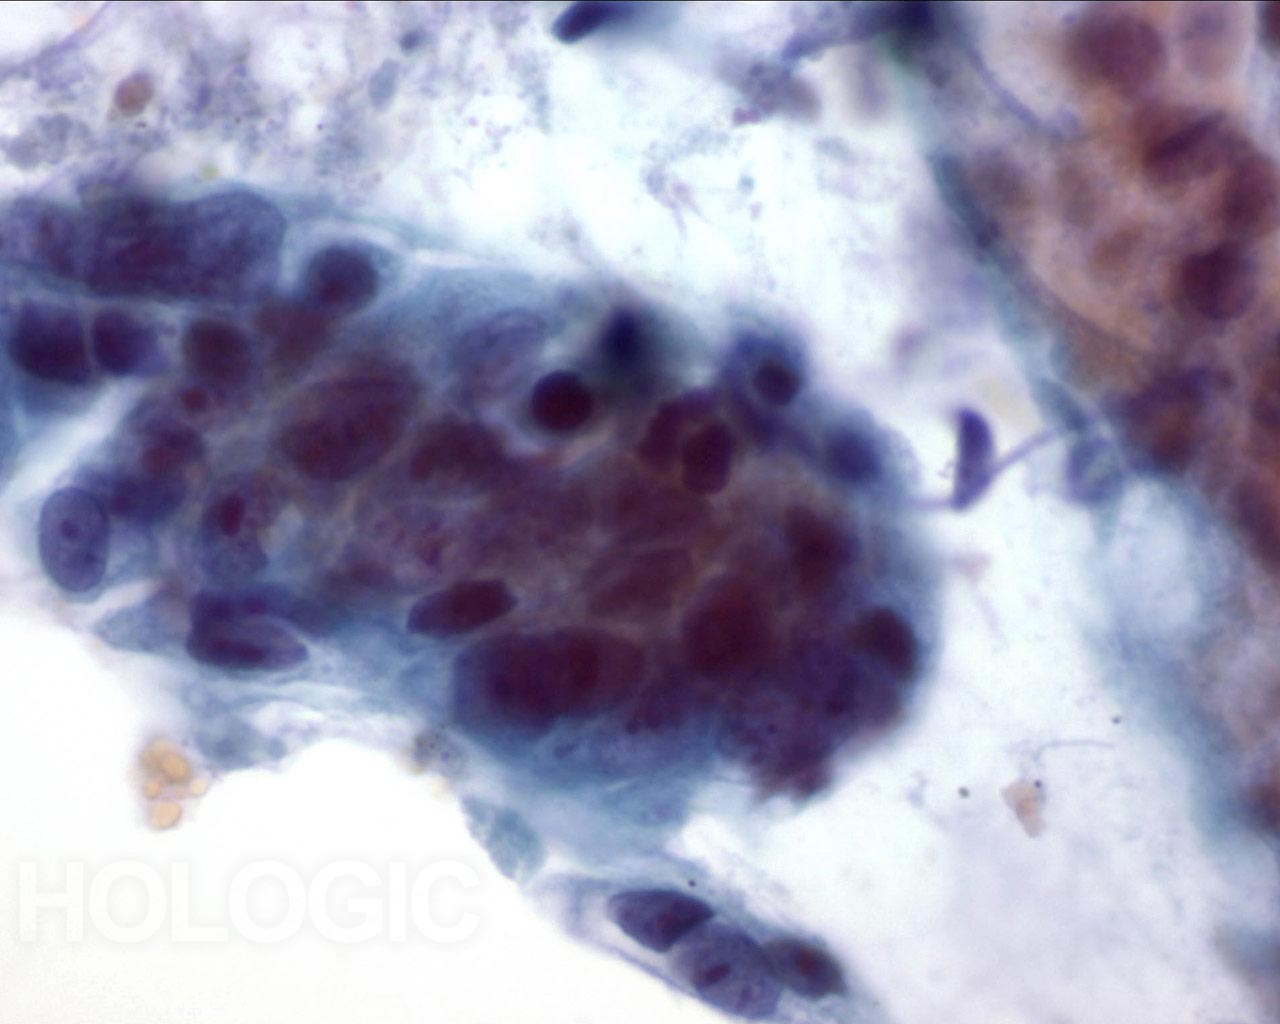

Abbildung 19

Bürstenabstrich des Kolons, Adenokarzinom des Kolons.

Bei starker Vergrößerung sind Pleomorphie, Zelldrängeln und Zellüberlagerung zu erkennen.

60x